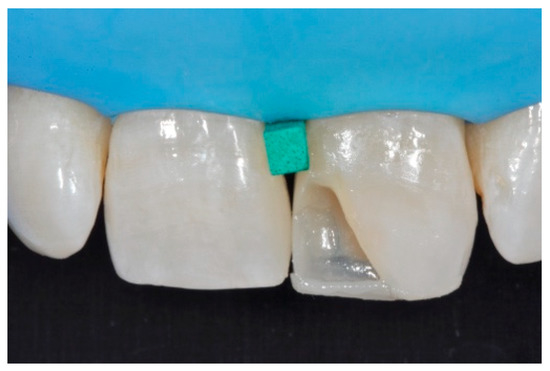

Once completed, the two frames (Clearfil Majesty ES-2, A1E, A2D, Kuraray Noritake Dental, Tokyo, Japan) showed internal and external excesses that were reduced using diamond burs and discs (Figure 33 and Figure 34) strictly following the procedure described in Section 2.1.2 of present article. Excesses were removed from the distal-incisal angle of #2.1 allowing therefore to obtain the desired translucency. After silane application and bonding procedure (Figure 35) as described in Section 2.1.2, restorations were completed (Figure 36 and Figure 37). They both show satisfactory clinical integration 1.5 years post-operative (Figure 38 and Figure 39).

Figure 35.

The modified frames treated with silane coupling agent and adhesive, ready for layering of dentinal body. Reprinted from Restauri diretti nei settori anteriori, G. Paolone, S. Scolavino, © 2021, with permission from Quintessence Publishing Italy.